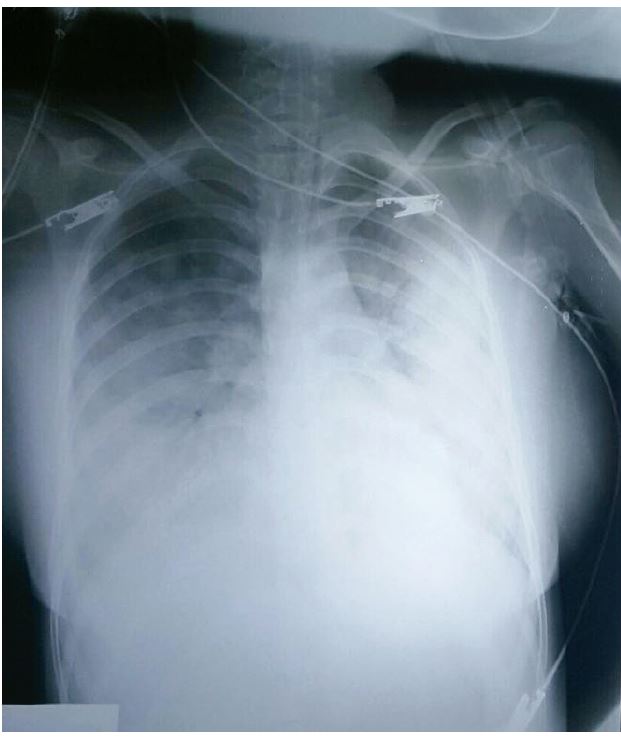

Figura 1: Radiografía de tórax

La paciente fue admitida en la unidad de cuidados intensivos pediátricos donde se le realiza una radiografía de tórax con hallazgos compatibles de edema pulmonar (ver figura 1). Su presión arterial gradualmente fue mejorando, por tanto, se remueve la ventilación asistida y las aminas vaso activas, al segundo día. Al tercer día, se suspende el inotrópico y es trasladada a una sala clínica. Al sexto día de manejo, se realiza una radiografía control (ver figura 2), donde se observa una importante mejoría. En consecuencia, es egresada.